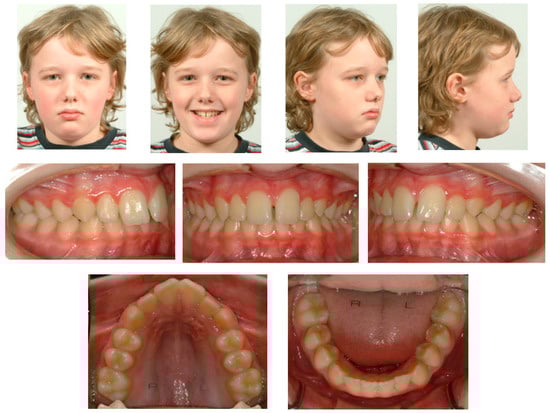

A 21-year-old Caucasian male presented with aesthetic complaints regarding his upper front teeth. He previously underwent orthodontic treatment for a deep bite at the age of 9 years and 11 months for 2 years and 11 months. He was treated with high-pull headgear (Headgear, Dentsply GAC International, NY, USA) followed by full fixed appliances (3M Victory Series APC conventional twin brackets, 3M Health Care Division, London, Canada), and flexible spiral wires (0.0195-inch, 3-strand, heat-treated twist wire, Wildcat, GAC International, Bohemia, NY, USA) were bonded to all the anterior teeth between 13–23 and 33–43 to stabilize the end result (Figure 2). Over the last few years (the moment of onset was unknown), he noted a continuing shift in the position of his upper front teeth (Figure 3A). Aside from his aesthetic complaints, he was concerned that the situation would deteriorate. With regard to his medical history, he only used antihistamines for hay fever if necessary. There was no record of dental trauma, and he was unfamiliar with oral parafunctions. The failure of the fixed retainers had never occurred, and he did not experience any pain or functional constraints.

Figure 1. Extra-oral and intra-oral photographs before first orthodontic treatment.